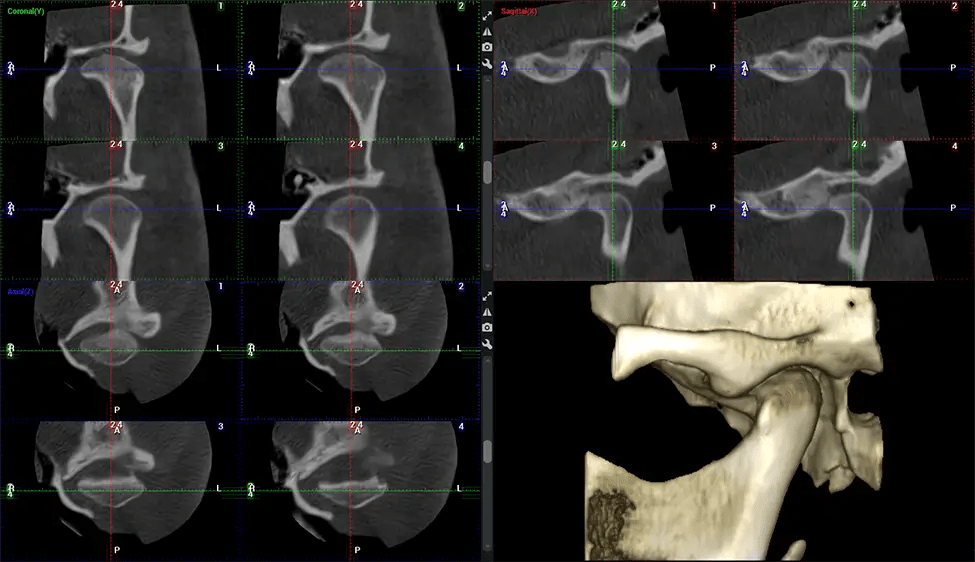

This 3D scan, called cone beam computed tomography, gives your dentist a more complete image of your oral anatomy and disease processes than a traditional X-ray. Unlike conventional X-rays, which capture a 2D image of your mouth from various angles, a 3D scan takes multiple digital X-rays for one image. It provides a complete view of your jaw, teeth, nerves, and soft tissues. This enhanced view allows dentists to detect minor issues not visible in traditional 2D scans, such as impacted wisdom teeth or bone fractures in the sinus cavity.

There are many benefits to using CBCT technology, especially compared to the traditional 2D X-ray format. One of the most significant advantages of CBCT scans is that they provide much more information than traditional X-rays. A scan lets your dentist see images from all angles of your jaw and mouth, including your sinuses, nasal cavity, cheekbones, and other surrounding areas. This added information helps your dentist craft a comprehensive treatment plan that addresses all aspects of your oral health.

Another significant benefit is that 3D imaging provides more precise images of your bone structure. These images are more detailed, providing you with a more accurate diagnosis. An accurate diagnosis means better treatment for you.

Planmeca Viso G7 CBCT ( Cone Beam CT Scan ) is designed to surpass the demands of industry leaders, specialists, and large institutions. It’s has a large ø25×30 cm sensor with four built-in cameras. It can capture unlimited volume sizes from a ø3×3 cm to a ø30x30cm volume capturing the skullcap through C7 on the cervical spine. The Planmeca Viso G7 offers the industry’s largest single volume scan of ø30×19 cm. It’s poised to handle advanced imaging modalities such as Planmeca ProFace® and Planmeca 4D™ Jaw Motion technology. The occipital head support allows an unimpeded view of facial tissue.